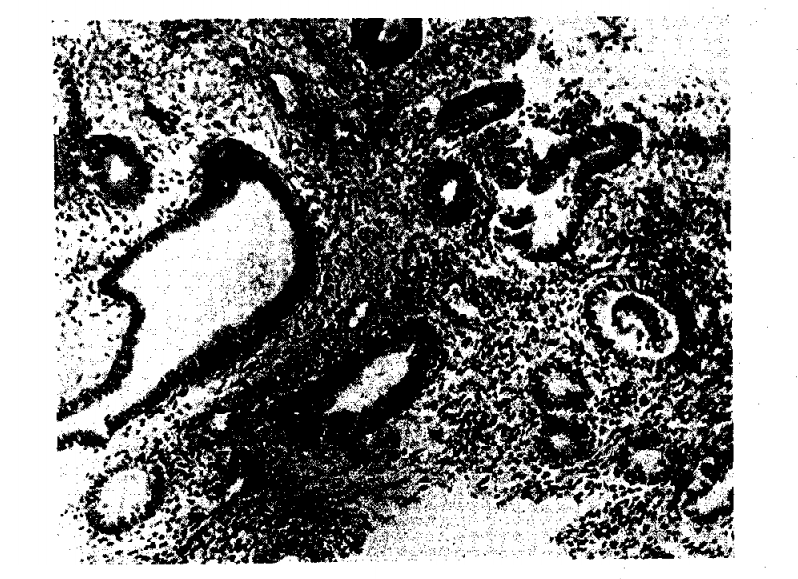

M. R., aged 35 years, had menopause precox. Her last menstrual period occurred in December, 1935. Hot flushes occurred 3 to 4 times daily. There were malaise and absence of libido. Previous therapy: Sporadic treatment with injections of estrone for two years. No effect on general condition. Implant: Aug. 15, 1940, 55 mg- of estrogen. Smears: August 15, typical castration cells; September 26, very good estrogenic function. Biopsy: Oct 11, 1938, atrophic endometrium (Fig. 1). Oct. 3 and 17, 1940, proliferative endometrium (Fig. 2).

Figure 1. Endometrial biopsy before therapy; nontimctioning endometrium cystic glands. Dense stroma.

Figure 2. Seven weeks after implantation of 55 mg, of estronic pellet. Moderate proliferation of endometrial glands, showing effect of mild estrogenic activity.